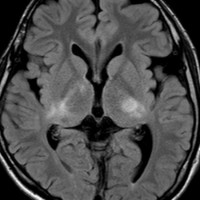

whole optic pathway pilocytic astrocytomaとは

両側の眼窩内視神経から視交叉、視索,外側膝状体,内包後脚,視放線近位部までが腫瘍化しています。FLAIRで高信号で,不規則にガドリニウム増強されます。これを手術摘出したり生検したりしても無駄です。放射線治療は不可能であり治療方法は化学療法のみです。

この子はCDDP/VCRの化学療法から開始して12年になりますが,今は無治療でわずかな視力ですが学校に通っています。優等生です。自然退縮を見ていますが,今後も変化する可能性はすこし残しています。